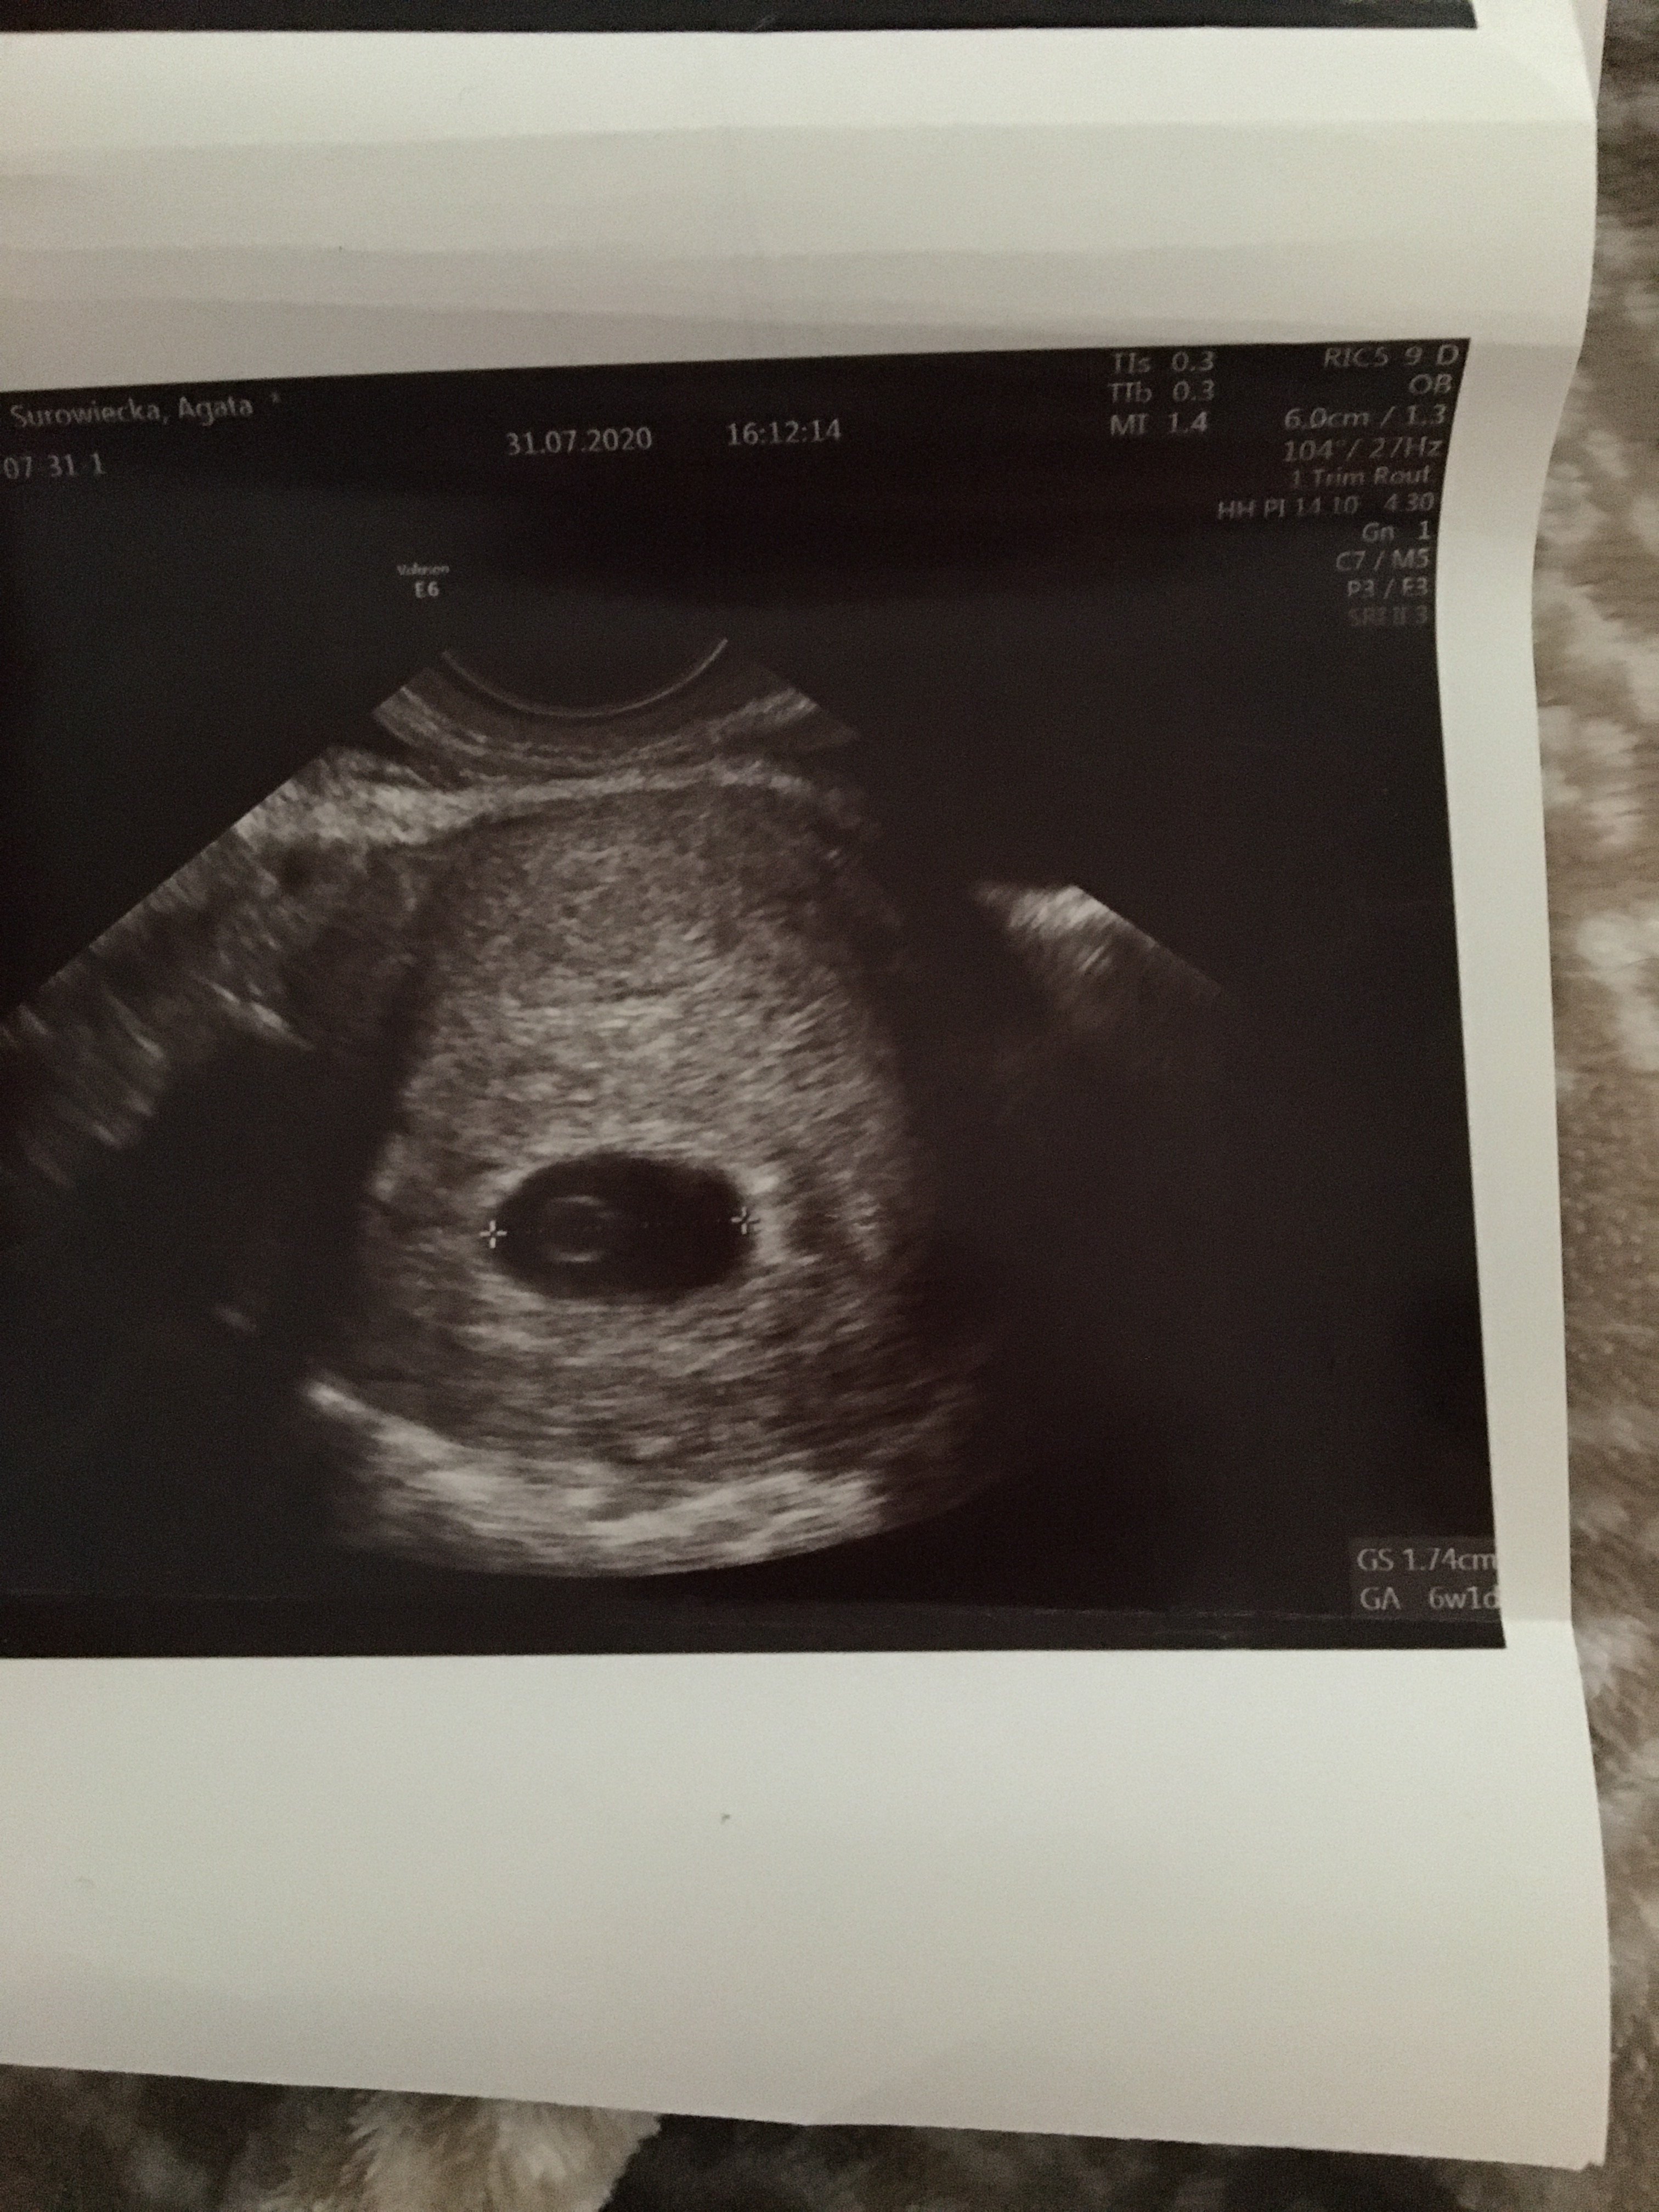

Dziewczyny z powodu plamienia trafiłam nagle do lekarza w piątek. Lekarz zrobił usg i według niego 6 tydz 1 dzień. Czy widać Tutajj zarodek ? Lekarz niestety mi tego nie wytłumaczył tylko pogratulował... czy powinnam się martwić ? Wiele z was pisze ze w 6 tygodniu słychać już serduszko

Tak, jest zarodek i ciałko żółte masz nawet wymiary podane na zdjęciach GS to pęcherzyk ciążowy, a CRL to wymiar zarodka:)